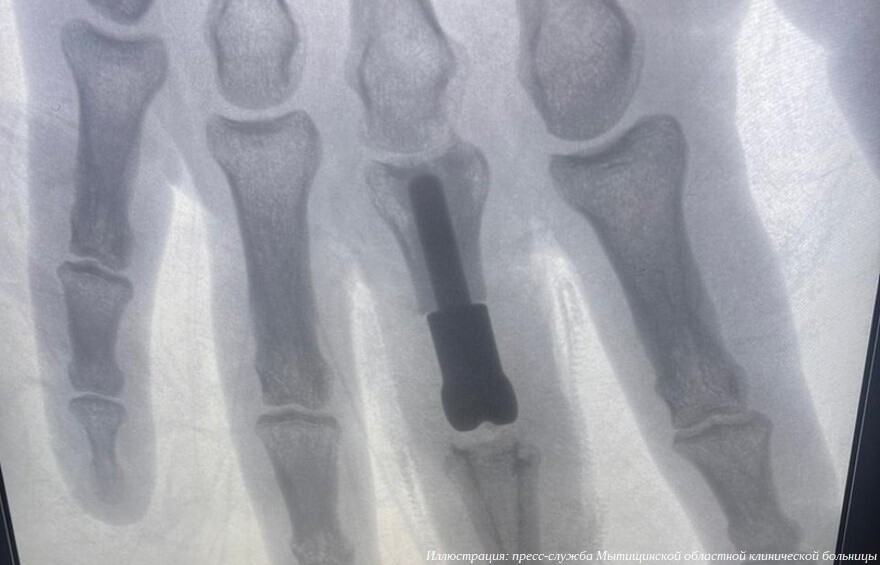

К хирургам-травматологам Мытищинской областной клинической больницы попал мужчина с открытым оскольчатым внутрисуставным переломом третьего пальца правой кисти. Это тяжелое повреждение, затрагивающее не только кости, но и межфаланговый сустав. Также были травмированы сухожилия, участвующие в разгибании пальца, и покровные ткани. Так как стандартные методы лечения не подходили, хирурги заменили поврежденный участок индивидуально спроектированным 3D-печатным титановым протезом.

Такую травму невозможно вылечить стандартными способами — гипсовыми повязками, остеосинтезом. В случае открытого, мелкооскольчатого перелома, когда восстановить суставные поверхности не представляется возможным, необходима замена поврежденного сустава на протез, но площадь поражения костей пальцев у пациента была значительной, установка стандартного эндопротеза привела бы к укорочению пальца и неудовлетворительному окончательному результату. Врачи пришли к решению о необходимости изготовления индивидуального эндопротеза, который смог бы заменить не только сам сустав, но и восполнить дефект основной фаланги пальца, сообщает пресс-служба медицинского учреждения.

«Протез напечатан из титанового порошка на 3D-принтере. Полученная конструкция учитывала все малейшие нюансы и особенности, которыми должен обладать имплантат, предназначенный для конкретного пациента. В России в настоящее время есть уже несколько биометрических лабораторий, которые занимаются подобной инновационной деятельностью.

За точность размеров компонентов и их форму отвечал биоинженер. Задача хирургов заключалась в установке созданного эндопротеза и проведении пластики поврежденного сухожилия. Операция прошла успешно», — рассказал хирург-травматолог Алексей Сизиков.